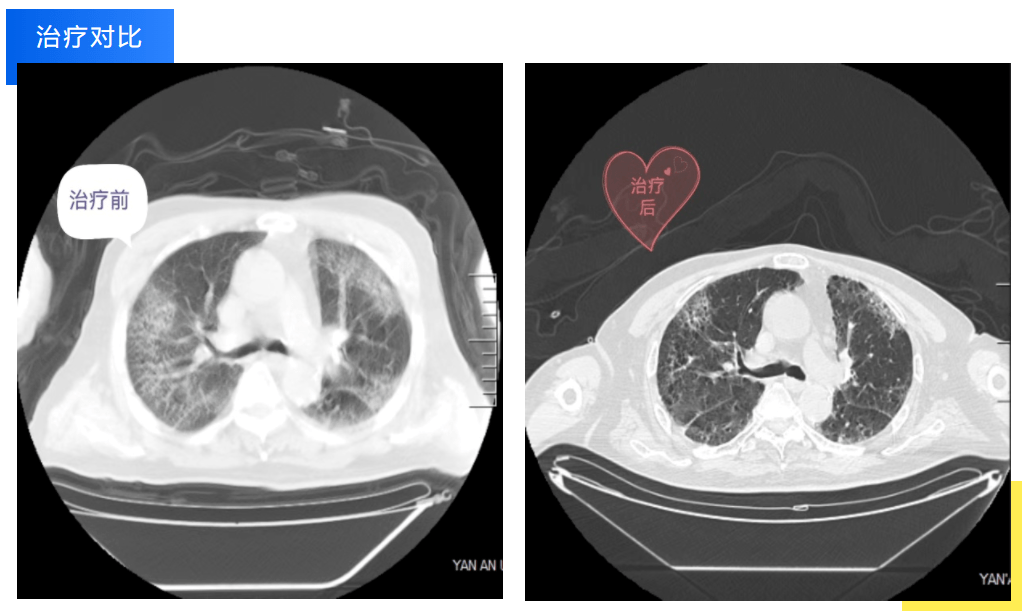

近期,患者張爺爺因重癥肺炎入住我院重癥醫(yī)學科。入院時,老人的病情已經進展為嚴重呼吸衰竭合并雙側胸腔積液,住院期間老人因對病痛的恐懼和對醫(yī)護工作的不理解而異常躁動不安,對診療及護理工作配合度極低,導致早期治療效果并不理想。重癥醫(yī)學科宋海剛主任帶領醫(yī)護團隊組織了科室疑難病例討論、全院多學科會診,張燕護士長、主管醫(yī)生屈曼曼細致地觀察病情,迅速梳理病情,調整診療方案,給予氣管插管、機械通氣、俯臥位通氣、抑制炎癥反應等綜合治療。

經過數(shù)日的治療和精心護理,老人呼吸衰竭的指標較前有了明顯的改善,氧合指數(shù)也從一開始的小于100mmHg逐漸提升到300mmHg以上,老人也感受到了醫(yī)護人員的良苦用心,從開始的抗拒到逐漸主動配合診療工作,目前已順利轉入下級醫(yī)院繼續(xù)康復。